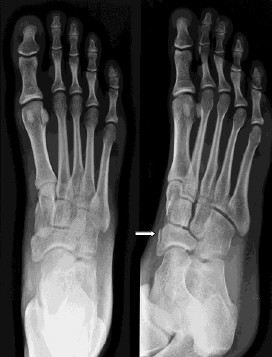

• Rontgen untuk mengevaluasi tulang dan menemukan lokasi fraktur